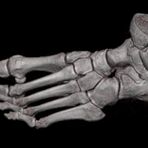

Extremitäten

• bei komplizierten Frakturen z. B. in der Nähe von Gelenken oder im Bereich der Handwurzel und Fußwurzel

• besonders hochauflösende, strahlendosissparende Darstellung aller Skelettstrukturen